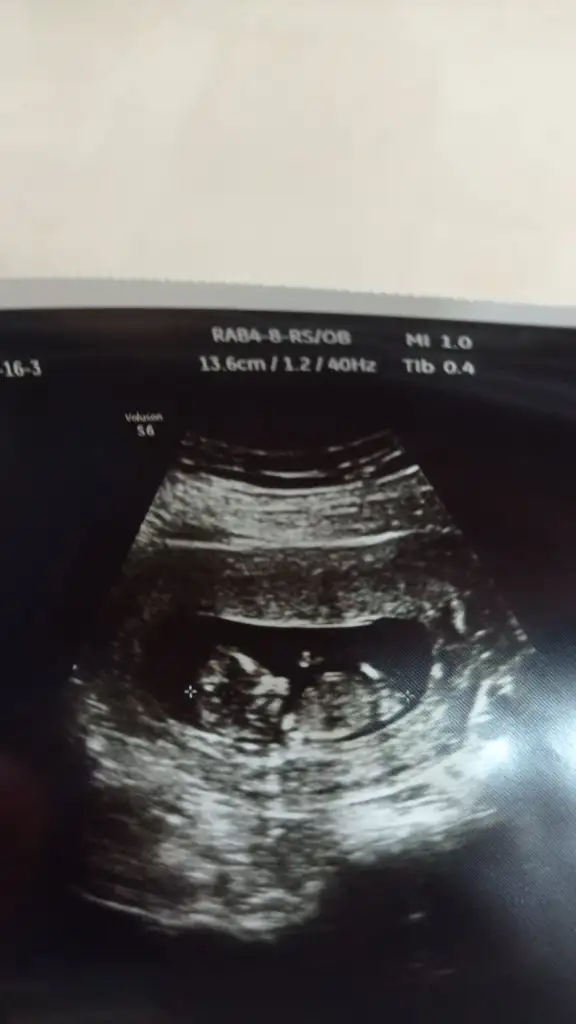

Merhaba karından ultrason bizi de bakabilir misiniz

Merhabaaaa, 7+5 tahmin alabilir miyimmm karından ultrason